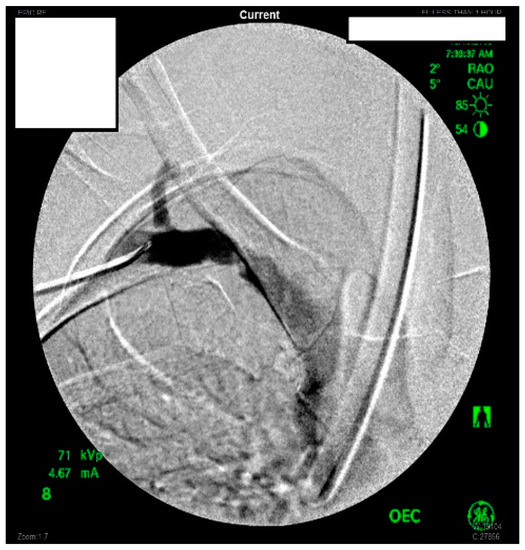

She underwent venography of the right arm venous system which revealed a 70–80% stenosis of the right subclavian vein in neutral position (Figure 1 and Figure 2). The vein was completely occluded in stress position. This was confirmed with intra-vascular ultrasound (IVUS). On IVUS measurements, the neutral position yielded a 74.4% stenosis while the stress position yielded 100% total occlusion (Figure 3 and Figure 4). It was noted that the contralateral vein appeared compressed in the costochondral space as well, though she was asymptomatic.

Figure 2.

Venogram demonstrating a right subclavian vein that is nearly occluded while in stress position.